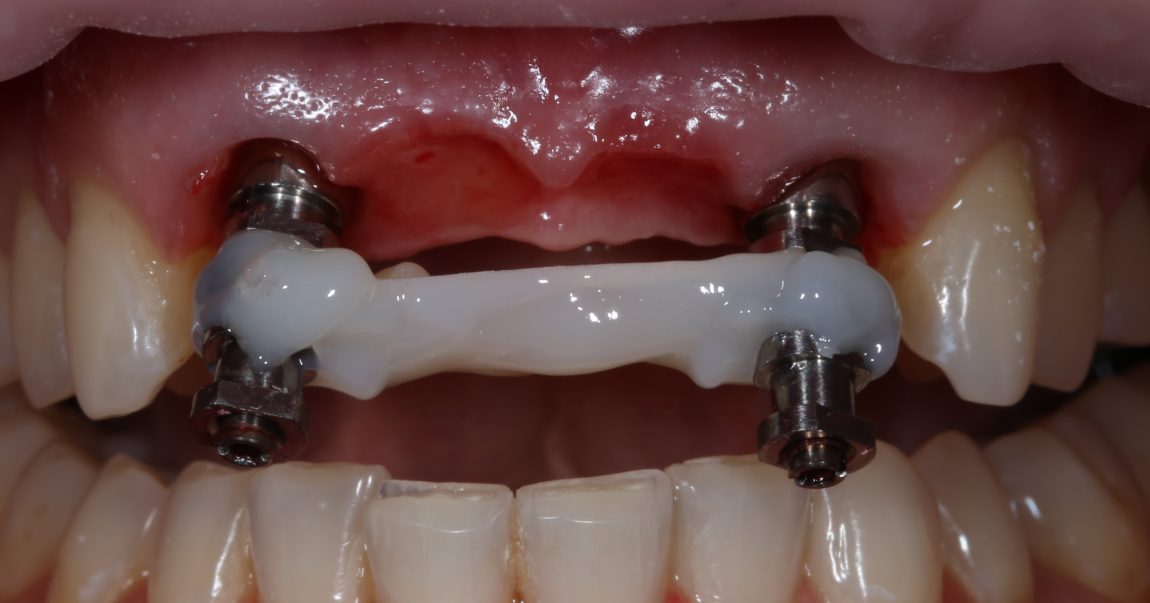

Фиксируем Esthetic Cap на имплантаты. Усилие при установке — 14 Нсм (больше ключ Xive не позволяет):

Еще раз проверим позиционирование имплантатов:

Поскольку трансгингивальная часть временного абатмента Esthetic Cap полностью перекрывает апертуру лунки зуба, мы можем обойтись без швов. Вообще без швов.

Теперь нужно сделать контрольные снимки, чтобы убедиться, что абатменты сели на платформу имплантата. В нашем случае, абатменты пришлось подточить: